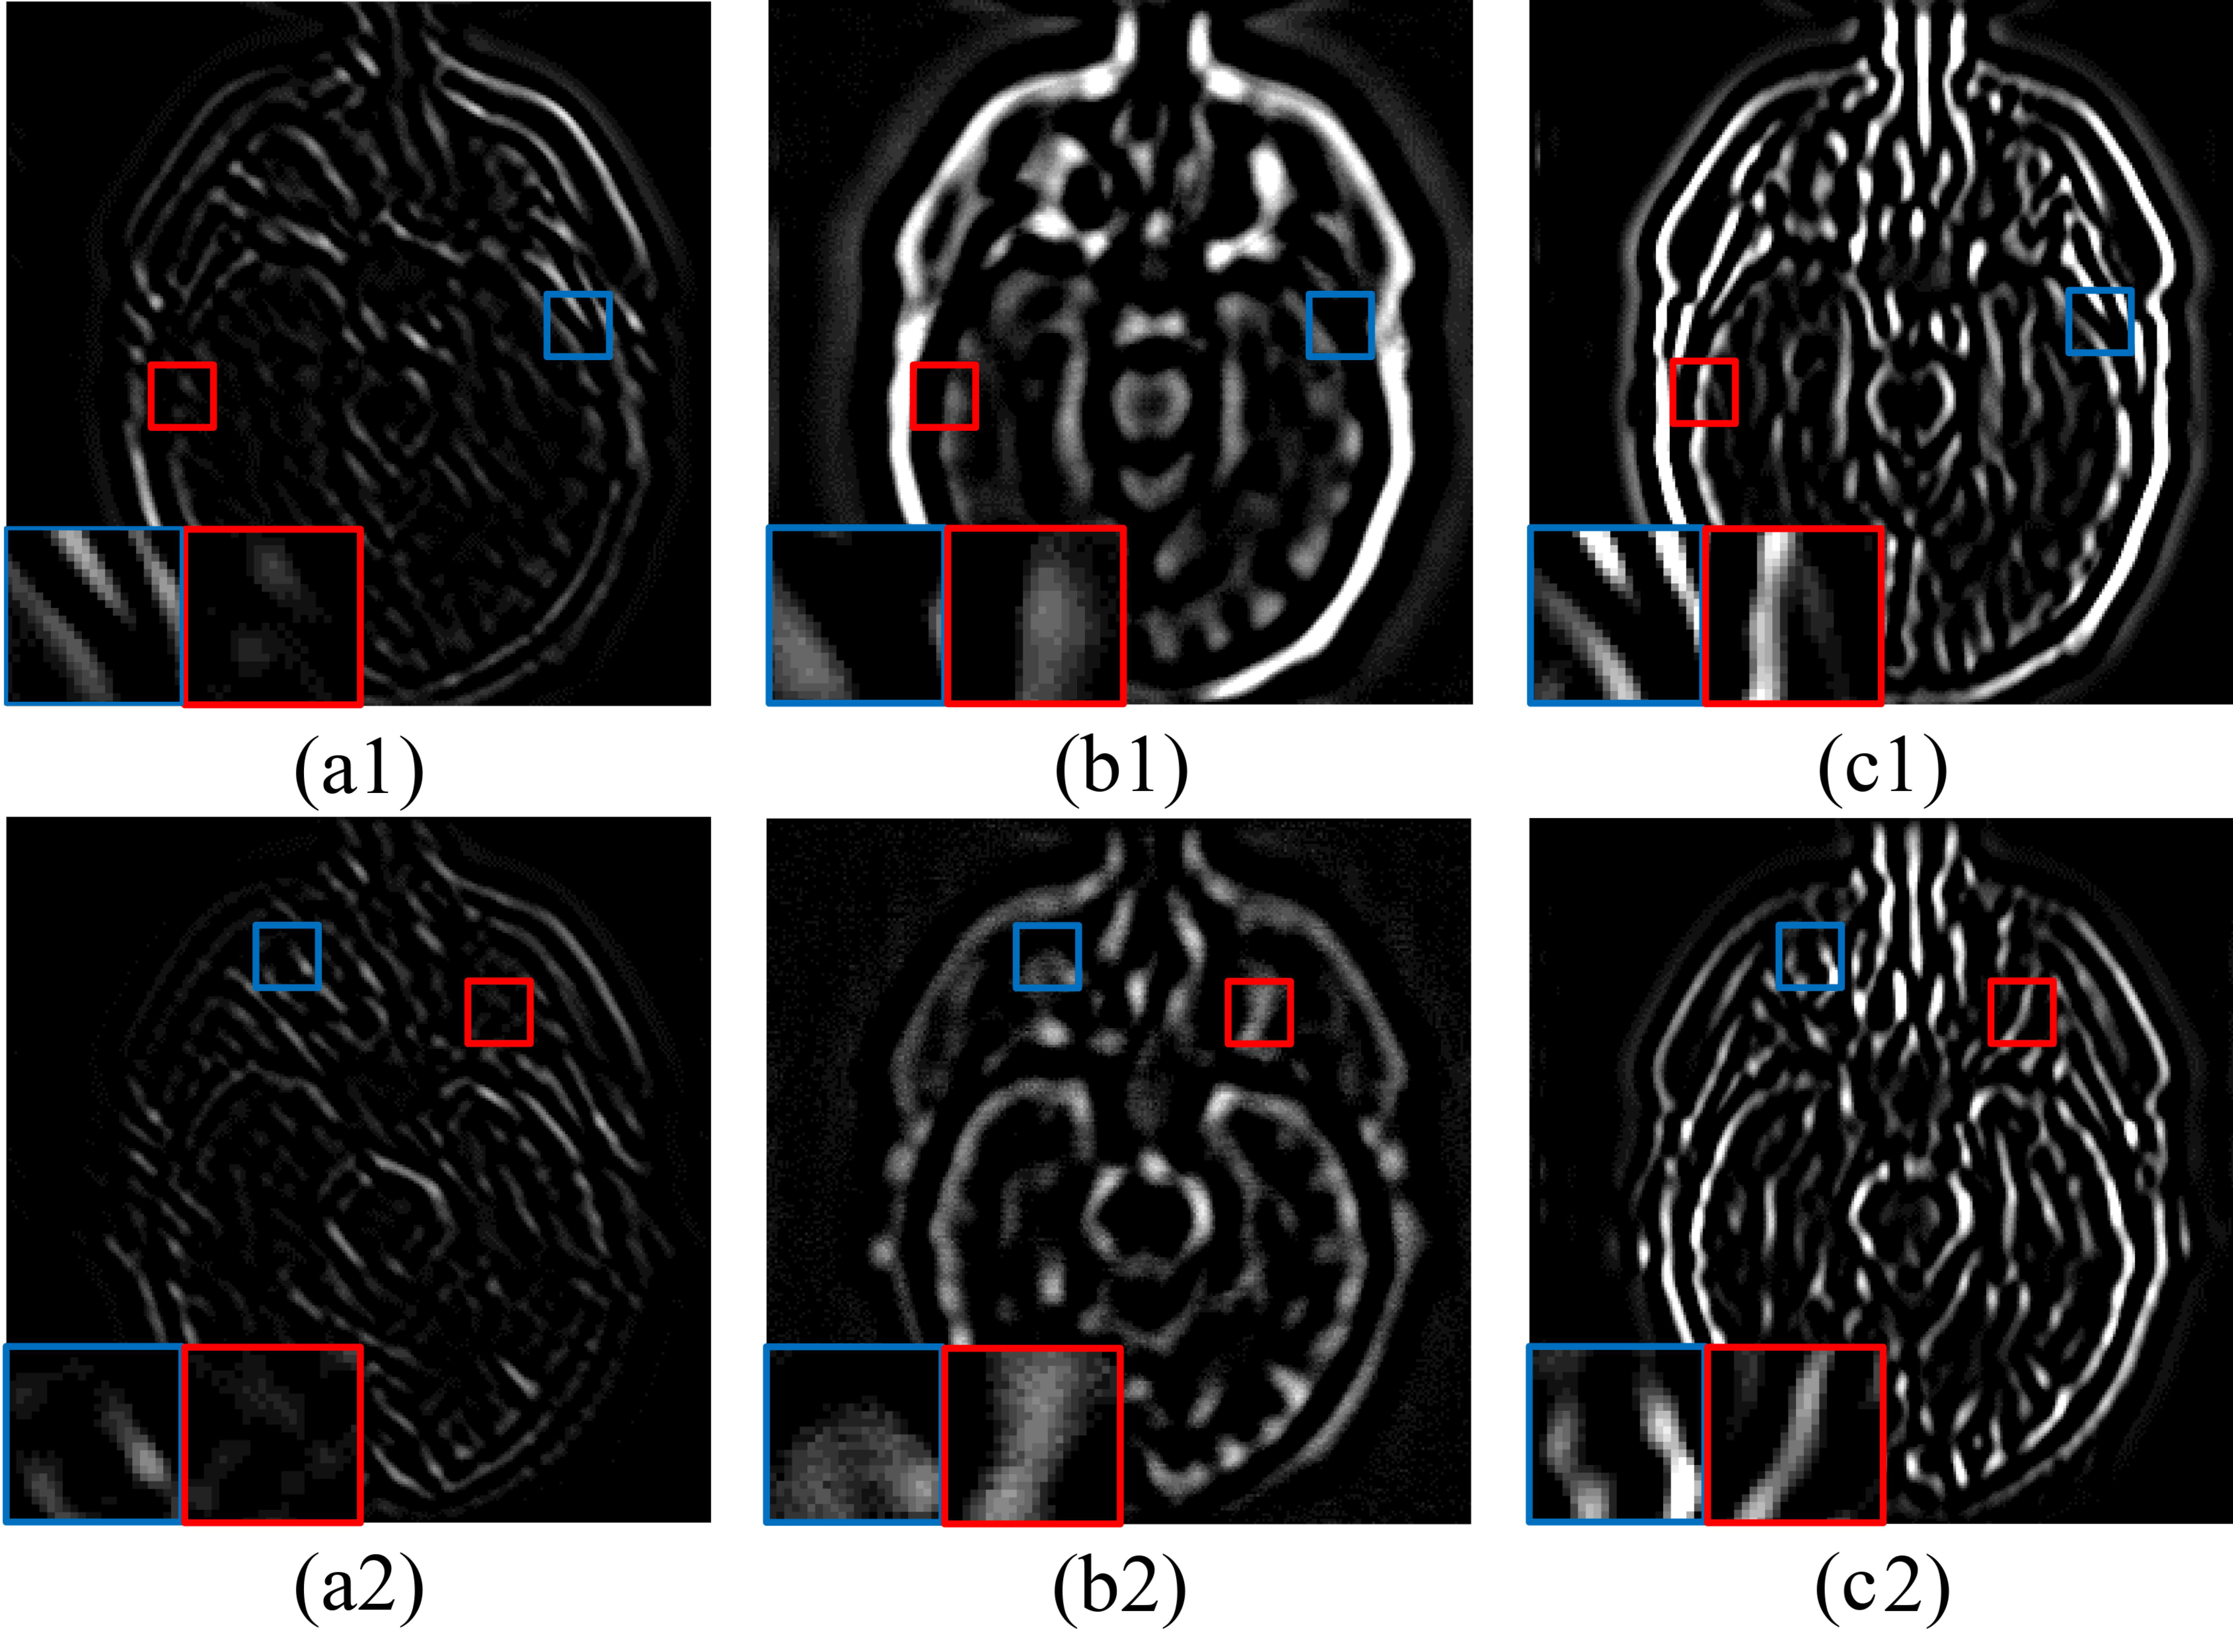

4.4. High-Frequency Completion

4.4.1. Joint Static and Dynamic Guidance

4.4.2. Fusion of Complete Mixed-Frequency Maps

5.2.1. Fusion Analysis on T1-T2